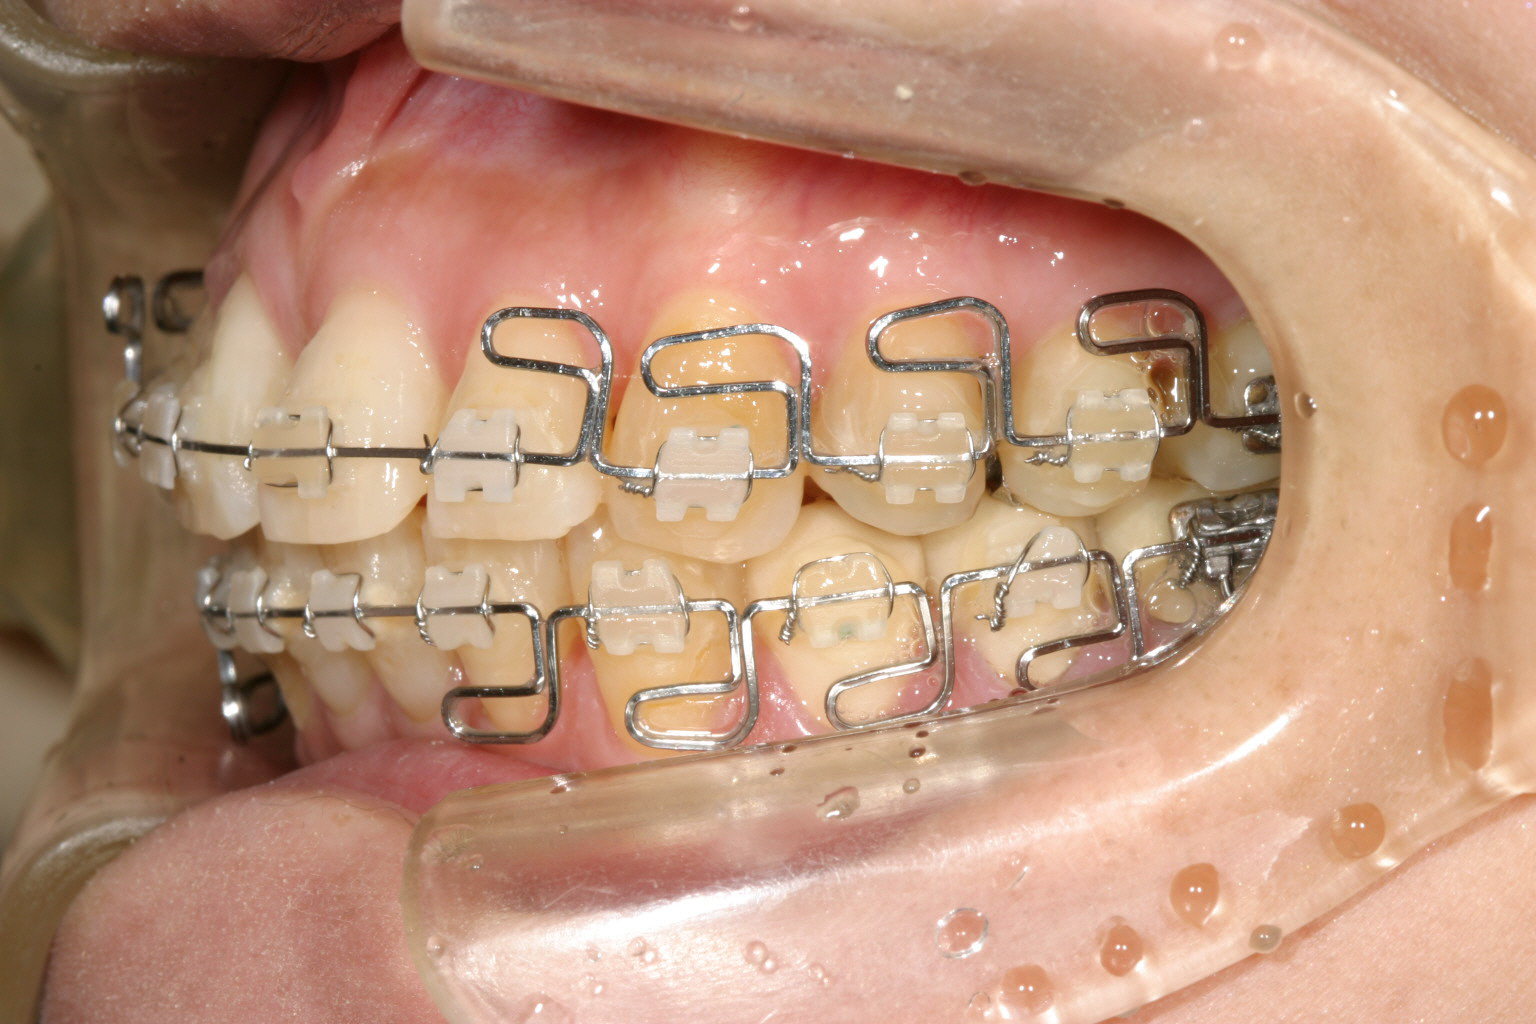

綺麗に並びました。

綺麗に咬合してます。 最初の正面観見て頂ければ正中が左にシフトし改善しているのが分かります。

こちらの症例は顎偏(顎偏移)に伴う顎関節症の治療例です、この様に誤った臼歯部冠補綴による顎関節症はよく見られます。

この様に補綴が原因であればその原因となる補綴物を入れ替える事で簡単に顎位の変更が出来、その後マルチループワイヤーで噛み合わせ修正しました。

と言う事で顎関節症は顎位改善により完治致しました。